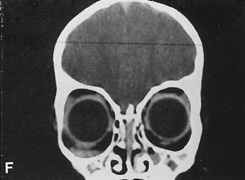

The transcranial orbitotomy uses a frontal craniotomy with removal of a portion of the orbital roof to expose the orbital apex or superior orbit. This is best performed by a neurosurgeon familiar with skull-base surgical approaches. In most cases, the supraorbital rim over the involved side is removed en bloc with the frontal bone flap (Fig. 13). The anterior one-half or two-thirds of the orbital roof breaks free with removal of the rim and frontal bone flap, and the remaining posterior portion of the roof can be removed with rongeurs. Historically, it was suggested that all orbital tumors be removed via craniotomy, because before the imaging era it was difficult to anticipate the intraorbital location of a mass.18 The transfrontal approach was first described by Jones10 in 1970. Jane and colleagues19 proposed the current technique in 1982. Refinements have been discussed by Maroon and Kennerdell9 and Housepian.20 This operation has been termed the panoramic orbitotomy by Rootman21 because of the wide area of exposure offered by this procedure.

Fig. 13. Schematic diagram for transcranial orbitotomy in which the supraorbital rim is removed en bloc with the frontal bone flap. This provides extensive exposure to the superior and lateral orbit.

Fig. 14. A,B. Large intraorbital lymphangioma causing proptosis and optic nerve compression in a 2-year-old child. C. View of the left orbit from above after removal of the frontal bone flap, including the supraorbital rim and orbital roof. An extensive exposure of the entire superior and lateral orbit is afforded. The levator and superior rectus complex is being retracted laterally with a muscle hook, whereas the Freer elevator retracts the superior oblique muscle medially. The frontal nerve can be seen running from posterior to anterior over the superior orbit. The orbital mass is exposed in this fashion. D. The fronto-orbital bone flap is wired back in place after completion of the procedure. E. Postoperative appearance of the patient. F. The postoperative CT scan shows complete removal of the lymphangioma. This large and diffuse lesion would have been difficult to remove with any other approach.

A burr hole is placed in the midline just above the orbital rim. This burr hole usually enters the frontal sinus. A second burr hole is placed anteriorly in the temporalis fossa at the junction of the cranium and orbit so that both compartments are exposed. Two or three additional holes are made in the frontal bone connecting the first two holes. The orbital rim is cut from the midline inferiorly, and the lateral orbital rim is cut from the temporalis fossa anteriorly. The dura is freed from the undersurface of the bone flap and is elevated superiorly, and the orbital roof is cracked off. The frontal bone, orbital roof, and supraorbital rim break off in one piece. The brain is retracted superiorly, and the remaining orbital roof is removed with bone rongeurs (see Fig. 14C).

After removal of the bony roof, the periorbita is visible. Typically, the periorbita is thin, and the levator rectus muscle and frontal nerve are visible beneath it. If exposure of the posterior optic nerve is desired, the dura can be elevated over the optic canal. The canal can be unroofed to decompress or explore the optic nerve, and the dura may be opened to view the intracranial optic nerve and the chiasm. At the orbital apex, the annulus may be cut to allow more anterior dissection and removal of the optic nerve in cases such as optic nerve glioma or meningioma. Because the superior orbital fissure and its contents lie lateral to the nerve, the intraconal space is entered on the medial side of the optic nerve. The orbital dissection can be carried out with a minimal amount of brain retraction after the en bloc removal of the frontal bone, supraorbital rim, and orbital roof.

After the dissection, the dura is closed and the frontal bone flap is plated or wired back into position (see Fig. 14D). The orbital roof is functionally restored with the replacement of the bone flap. The sinuses must be sealed off with muscle, pericranium, or other tissue. The coronal flap is closed in layers. The postoperative appearance is unchanged because the bone flap is replaced in one piece. Problems with globe ptosis, enophthalmos, pulsatile proptosis, or meningitis are rare. However, extensive mobilization of the temporalis may result in cosmetically significant temporal atrophy. Orbital apical dissection often results in extraocular motility dysfunction as a result of traction on the third, fourth, or sixth cranial nerves, but cranial nerve function usually recovers unless the nerves have been transected.

Indications

Transcranial orbitotomy provides access to the superior two-thirds of all the orbital compartments (Fig. 15). In some cases, the craniotomy is used only to provide access to the orbit that is otherwise not possible, such as biopsy of an orbital apex mass. Its primary use is for exploration of tumors involving the orbital apex, or large tumors extending above and medial to the optic nerve. The transcranial orbitotomy also is used as part of combined procedures for approaching tumors involving the orbit as well as the anterior and middle cranial fossae. Most commonly, this involves sphenoid wing meningioma resection.

Fig. 15. Schematic of areas amenable to transcranial orbitotomy. Coronal (A) and axial (B) sections.

The transcranial orbitotomy offers unsurpassed exposure of the superior orbit, orbital apex, and chiasm. Its relatively low morbidity makes this orbitotomy the procedure of choice when safe, wide exposure of the posterosuperior orbit is necessary. It is not indicated for orbital apex lesions lying inferior to the optic nerve, in which an extended lateral orbitotomy and temporal craniotomy may be required.